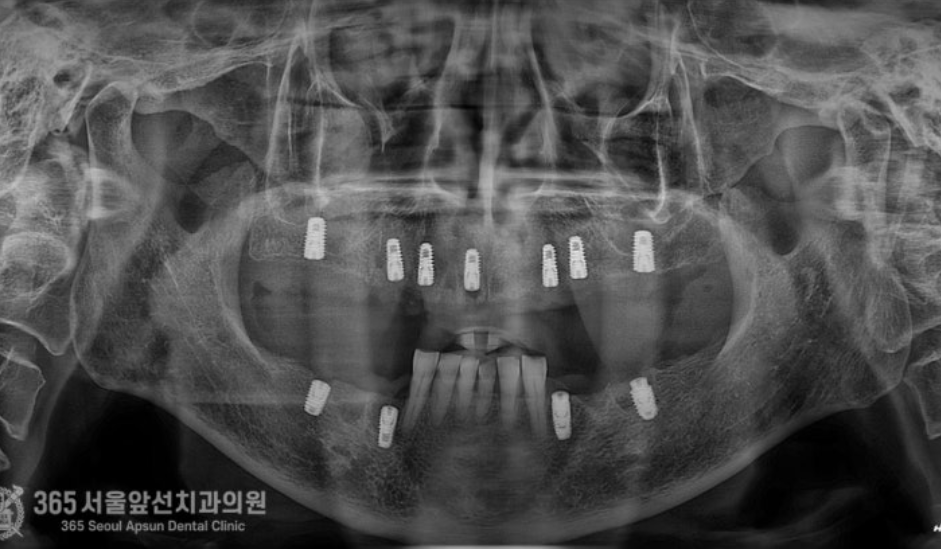

촬영일시 : 24.06.12 처음 내원 당시 엑스레이 사진입니다. 치아가 많이 없으시고 특히 어금니 쪽에는 뿌리끝에 염증이 많이 잡혀있어서 치아가 많이 불편하셨던 상태입니다.

촬영일시 : 24.07.09 의식하진정법(수면치료)을 이용하여 잠자는 듯한 상태에서 수술을 진행하여 위,아래 두 번에 걸쳐 수술을 마무리 해드렸습니다. 위턱에 발치를 동반하여 7개 임플란트 식립 및 뼈이식과 양측 상악동 거상술을 포함하여 총 32분이 소요되었으며, 아래턱에 발치를 동반하여 4개 임플란트 식립 및 뼈이식에 총 15분이 소요되었습니다. 수술은 서지컬 가이드나 기타 복잡한 장비의 도움없이 진행되었습니다. 수술은 아주 잘 끝났고 환자분도 정확하고 고통없는 수술에 매우 만족하셨습니다.